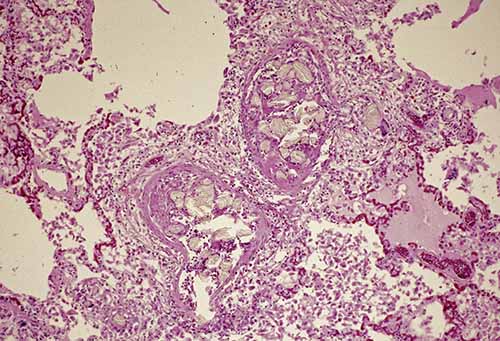

Amniotic fluid emboli are thought to enter the maternal circulation via a defect in the maternal/fetal interface, likely at the level of the endocervical veins, placental attachment site, or site of uterine trauma. Traditionally, it has been proposed that a pressure gradient favoring the entry of amniotic fluid should exist such as strong uterine contractions during labor. Components of embolized amniotic fluid may include epithelial squamous cells sloughed from fetal skin, mucin or bile pigment excreted from fetal intestine as meconium, adipose from the vernix caseosa, and lanugo hairs (Figures 24-13 and 24-14). Amniotic fluid emboli (AFE) are largely innocuous; the passage of fetal tissue into maternal vasculature at delivery appears almost ubiquitous, and arterial catheterization studies have shown that 20%–100% of pregnant women without syndromic manifestations have squamous cells in their pulmonary arterial circulation.

The gross findings with AFE syndrome are usually non-specific but may include pulmonary edema or congestion, atelectasis, or hyperinflation. Stigmata of DIC can be seen, although thrombi in the main pulmonary arteries or heart is atypical. Careful examination of the uterus and placenta should be performed. While not diagnostic of AFE syndrome, histologic detection of AFE can certainly provide helpful supportive evidence. Submission of multiple pulmonary histologic sections may increase likelihood of detection as AFE tend not to be uniformly distributed. Other organs/tissues in which AFE have been detected include uterus/cervix, heart, liver, spleen, kidneys, adrenal glands, pancreas, and brain. Special stains and immunohistochemical markers that may prove helpful in detecting AFE include cytokeratin AE1/AE3 (squamous epithelial cells), oil red O on frozen tissue (adipose), Alcian blue PAS or TKH-2 (mucin). Some studies have suggested that AFE syndrome may represent an anaphylactoid reaction with elevated postmortem serum tryptase levels being supportive evidence; however, other studies have found that serum tryptase has poor sensitivity for AFE syndrome diagnosis.